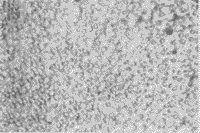

细胞培养3~5天后,细胞贴壁,体积小,圆形,分散存在,部分细胞有轴突伸展(照片1)。微波辐照后,Ⅰ组细胞发生聚集,仍可见轴突,细胞边界清楚(照片2);Ⅱ组细胞聚集成团,少数细胞散在,轴突消失,边缘较模糊(照片3),偶见“环状”细胞出现(照片4);Ⅲ组细胞与Ⅱ组相似,散在细胞较多;Ⅳ组细胞多数边界模糊,部分细胞漂浮,可见细胞碎片(照片5)。辐照后细胞继续培养48小时后,Ⅰ组细胞大部分散在,少量聚集(照片6),Ⅱ组细胞仍聚集成团,但细胞亮,边缘清楚,Ⅲ组变化不明显,Ⅳ组细胞减少,杂质多。

1 正常RGC形态(×250)

2 10mW/cm2(30min)辐照后细胞形态(×250)

3 10mW/cm2(60min)辐照后细胞形态(×250)

4 10mW/cm2(60min)辐照后凋亡样细胞(×400)

5 30mW/cm2(60min)辐照后细胞破坏较重(×250)

6 辐照后再培养48h的细胞形态(×250)

附图 微波辐照及再培养对细胞形态的影响